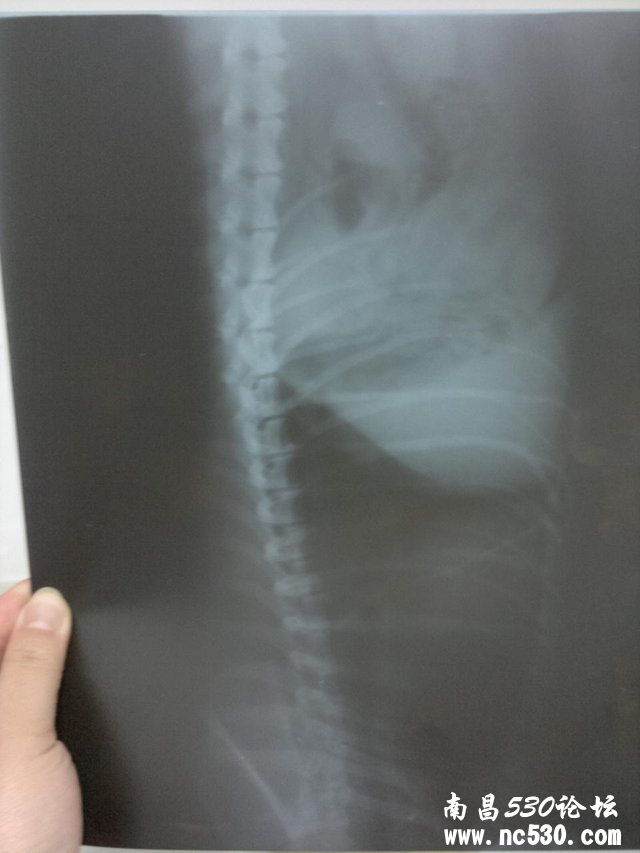

排便如何:正常,一天最少二回,形状颜色都很好 症状:大概有一个月了,没精神总爱趴着,有时呼吸间身体有轻微拌动,睡觉有时会喘几下,溜弯时不爱走近几天不爱吃饭. 12月18日在家附近的宠物诊所诊断说心肌肥大,第二天发现外阴流脓水诊断子宫蓄脓,后有医生说开放型的叫子宫内膜炎,现在打消炎针.  以下是12月18日的胸片

12月20日在一家医院输液,第一天效果挺好回家主动吃饭第二天就没精神了第三天刚打第一组能量就不行了浑身发抖医院马上打了强心剂,马上就不打了. 12月23日到我们这的农业大学动物医院,医生说它这种情况不能输液开了三针拜有利(每天0.5ML)12月26日恢复的特别好又补打了一针拜有利,医生说不用去了就是注意下次发情期就行了.

12月29日晚10点左右又出现舔外阴,大口喘气的情况,12月30日早10点多发现外阴有少量浓液流出,不吃饭不让人触摸下半身有发脾气的迹象.马上带去农大动物医院,14:00多打一针拜有利,一针缩宫素,头包点滴至17:00期间很安稳无异常是(就是没精神)外阴持续流出非常浓稠液体. 12月30日14:00测直肠内温39.5度 12月30日晚上吃了些饭(食欲可以) 12月31日10:00去医院复查没精神,下车后后腿无力有点支撑不住身体.10:00多打一针拜有利(0.4ML)医生诊断贫血,开补血口服液.回家后12:30分左右给狗服用12ML补血口服液.13:30左右吐了一回黄色的液体的水.估计是补血口服液.14:00喂了40ML婴儿米粉糊.之后不久开始大口喘气(注:今天一直不间断的大口喘气)14:29分又给服8ML补血口服液(至发贴没有吐出来)现在一直在喘,并且后腿无法支撑身体.(打点滴都是打在前腿上的) 好心医生给看是我家宝贝到底是怎么了.在线等救命!!!!!!